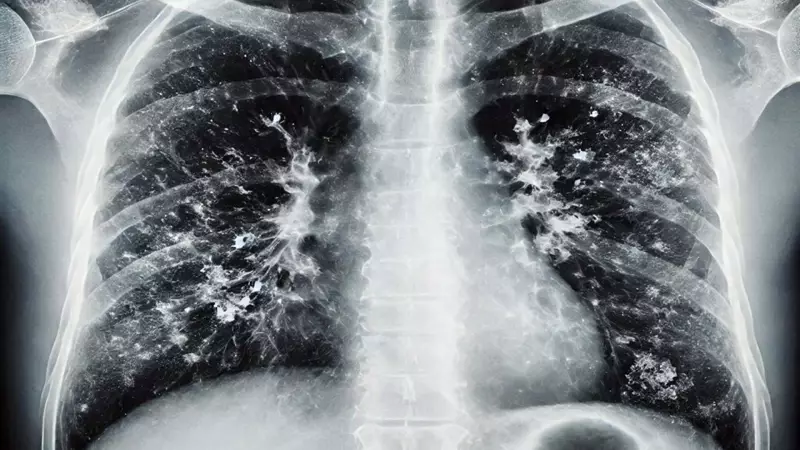

Özellikle 65 yaş üstü vatandaşlar için uyarılarda bulunan Şener, bu grupta RSV viral enfeksiyonunun önem taşıdığını belirtti. RSV'nin akciğerde yaygın enflamatuar tabloya sebep olduğunu ifade eden Prof. Dr. Şener, bu enfeksiyonun da aşısı olduğunu ve özellikle 75 yaş üstü bireylerin mutlaka bu aşıyı yaptırması gerektiğini söyledi.

Prof. Dr. Şener, "65 yaş üstünden başlarsak viral enfeksiyonlar ağır seyrediyor. Ciddi solunum yetmezliği, ateş, üşüme ve titreme semptomları; acil servise başvuru ve oksijen desteğine rağmen toparlanamama gibi durumlar görüyoruz" açıklamasını yaptı.

Hastalığı ayakta geçirenlere yönelik de değerlendirmelerde bulunan Şener, hafif geçirilen enfeksiyonların bile akciğerlerde kalıcı hasar bırakabildiğini belirtti. KOAH ve astım gibi rahatsızlıklara yol açabilen bu durumun ilerleyen dönemlerde ömür boyu ilaç kullanımını gerektirebileceğini ifade etti.